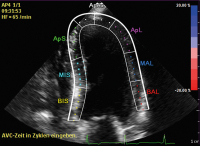

Echo - Bull's-Eye-View

Abbildung 4: Links: Bull’s-Eye-View mit allen 17 linksventrikulären Segmenten. Die Farbcodierung zeigt eine gute longitudinale Kontraktilität aller Segmente an. Der GLS beträgt –23,0 %. Rechts: zugehörige segmentale Strainkurven. Die Maxima der systolischen Kontraktion (= Minima der Kurven) fallen zeitlich zusammen (synchrone Kontraktion aller Segmente). Divergieren die Kurven hinsichtlich des zeitlichen Auftretens ihrer Minima, handelt es sich um eine dyssynchrone Kontraktion der linksventrikulären Segmente. Dies kann beispielsweise beim Vorliegen eines Linksschenkelblocks beobachtet werden